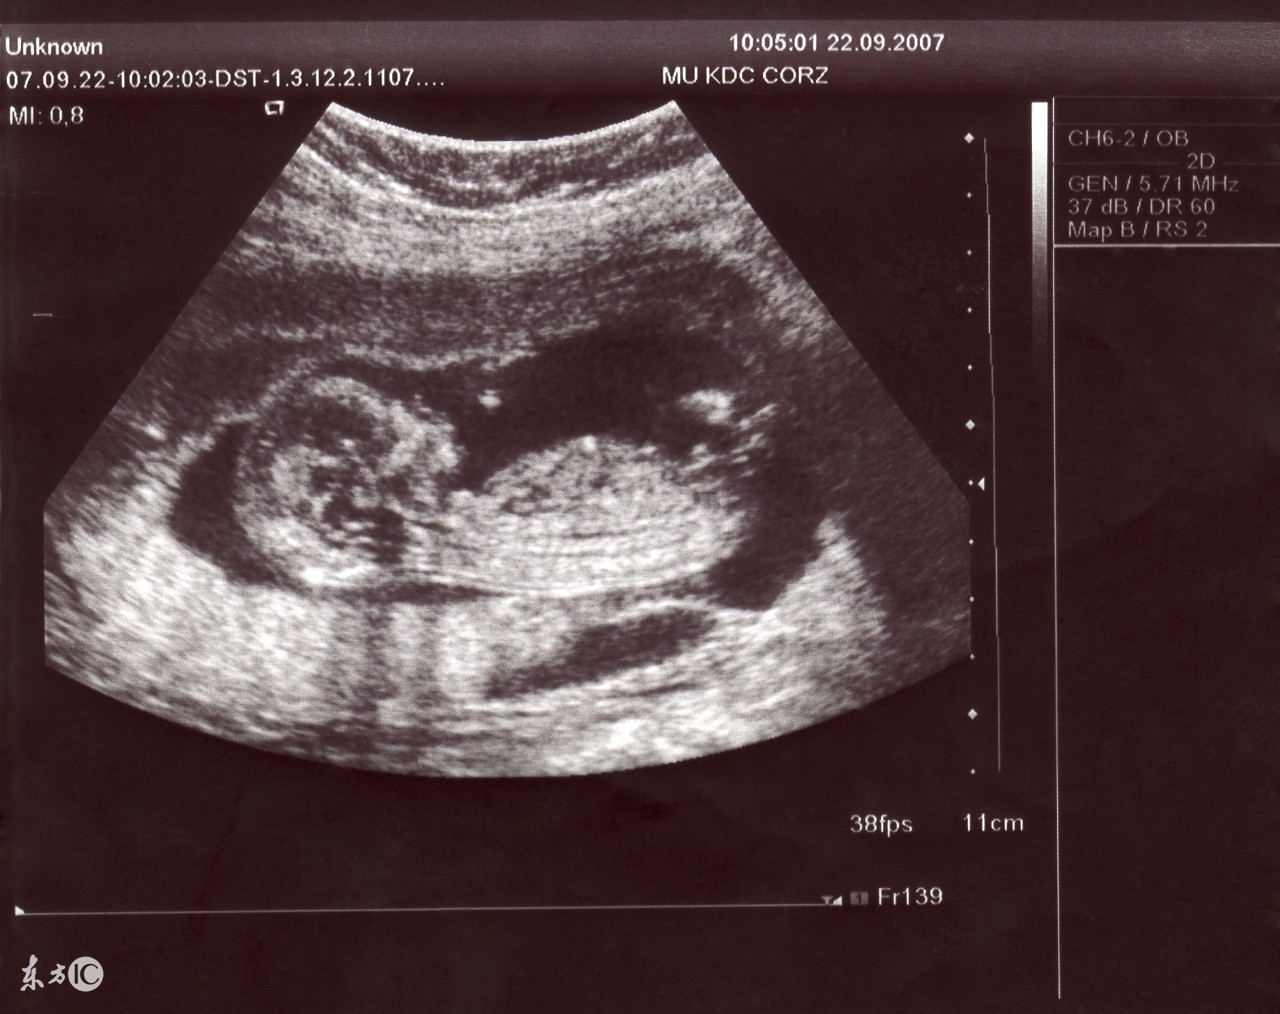

B超也就是超声波诊断,是利用一种超出人的听觉范围的频率的声音,它可以穿透物体,如果碰到障碍,就会产生回声,而各种不相同的障碍物就会产生不相同的回声。人们通过仪器将这种回声收集,并显示在屏幕上,可以用来了解物体的内部结构。利用这种原理,人们将超声波用于诊断和治疗人体疾病。

疑虑4:医生在做B超时会在屏幕前仔细研究半天,通过B超究竟能看到什么?

怀孕5个月后,通过B超就可以看到发育比较健全的胎儿了,如脸、五官、躯干、四肢,还有连接母体的脐带和胎盘等。